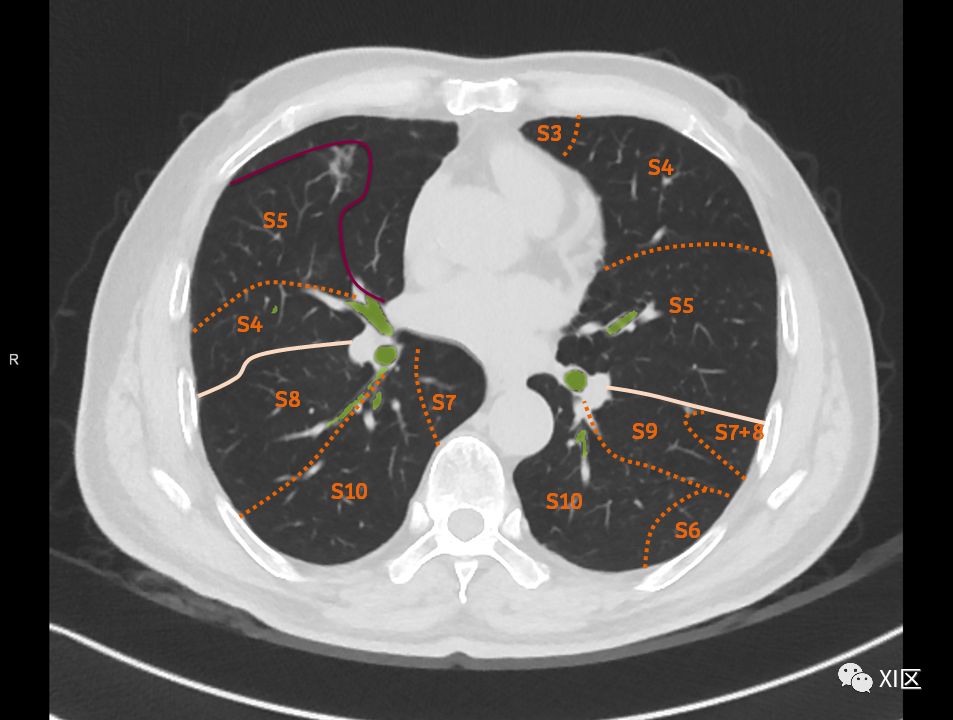

肺的断层分段示意图

在进行肺的分段时,可以上下观察浏览,沿着相应气管的走形可以更容易准确地进行分段。